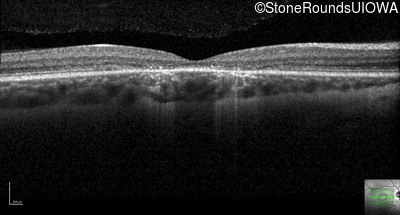

Optical Coherence Tomography - Right - 20/40 -2

Exemplar / OCT Stack

Optical Coherence Tomography - Left - 20/50 +2